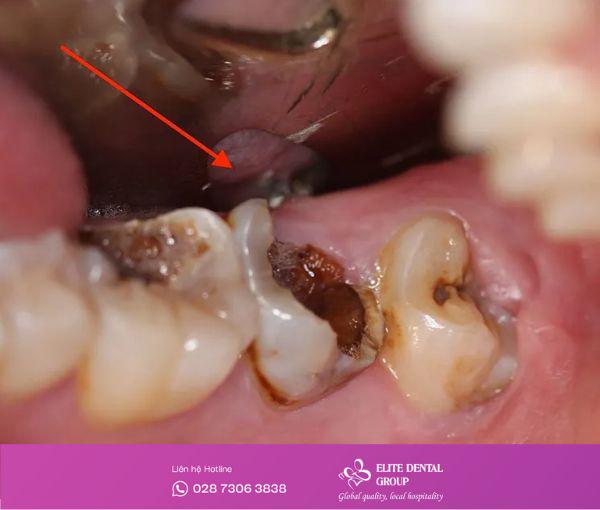

Răng sâu phá hủy cấu trúc nặng

Khi mô răng bị phá hủy nghiêm trọng, phần thân răng vỡ gần như toàn bộ hoặc chỉ còn lại chân răng yếu ớt, không đủ nền để trám hay bọc sứ, việc nhổ bỏ là điều bắt buộc. Nếu giữ lại, ổ sâu có thể lan rộng, gây viêm xương ổ răng và ảnh hưởng tới các răng kế cận.